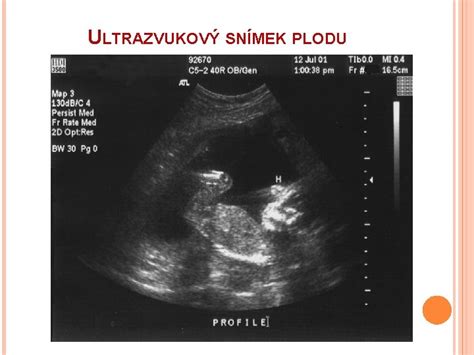

V tomto období sa často vykonáva prvé ultrazvukové vyšetrenie, ktoré potvrdí počet plodov, ich vitalitu a rozmery. V 13. týždni plod prehĺta plodovú vodu a vylučuje moč, čím vzniká mekónium - prvá stolica. V tomto týždni sa zvyčajne koná prvé veľké ultrazvukové vyšetrenie a absolvujú sa krvné testy, ktoré spolu s ultrazvukovými výsledkami slúžia na vylúčenie genetických vád, ako je napríklad Downov syndróm.

- Prvý ultrazvuk: Zvyčajne okolo 6.-8. týždňa, na potvrdenie tehotenstva a viability.

- Prvý prenatálny screening: Medzi 11. a 13. týždňom, ktorý zahŕňa ultrazvukové meranie šijového prejasnenia (NT) a krvné testy (stanovenie hladín PAPP-A a voľnej beta-hCG).

Ak žena zistí tehotenstvo v 5. týždni, mala by navštíviť svojho gynekológa, ktorý ju pošle na krvné testy na potvrdenie tehotenstva a objedná na prvý ultrazvuk okolo 6. alebo 7. týždňa. V 6. týždni môže prebehnúť prvé ultrazvukové vyšetrenie, ktoré býva vaginálne. Lekár skontroluje zväčšenie maternice a prekrvenie krčka maternice. Pri prehliadke sa meria tlak, hmotnosť a vyšetruje moč.

- Ultrazvukový screening druhého trimestra (morfologický alebo veľký ultrazvuk): Medzi 20. a 22. týždňom tehotenstva. Toto podrobné vyšetrenie sa zameriava na posúdenie morfológie plodu, hodnotí sa jeho veľkosť, proporcionalita, ako aj vývoj jednotlivých orgánových systémov (CNS, srdce, pľúca, tráviaci trakt, obličky, skelet). Lekár vyhľadáva prípadné vrodené vývojové chyby. Dôležitou súčasťou je aj hodnotenie množstva plodovej vody a polohy placenty. Meria sa aj dĺžka krčka maternice, najmä pri riziku hroziaceho potratu alebo predčasného pôrodu.